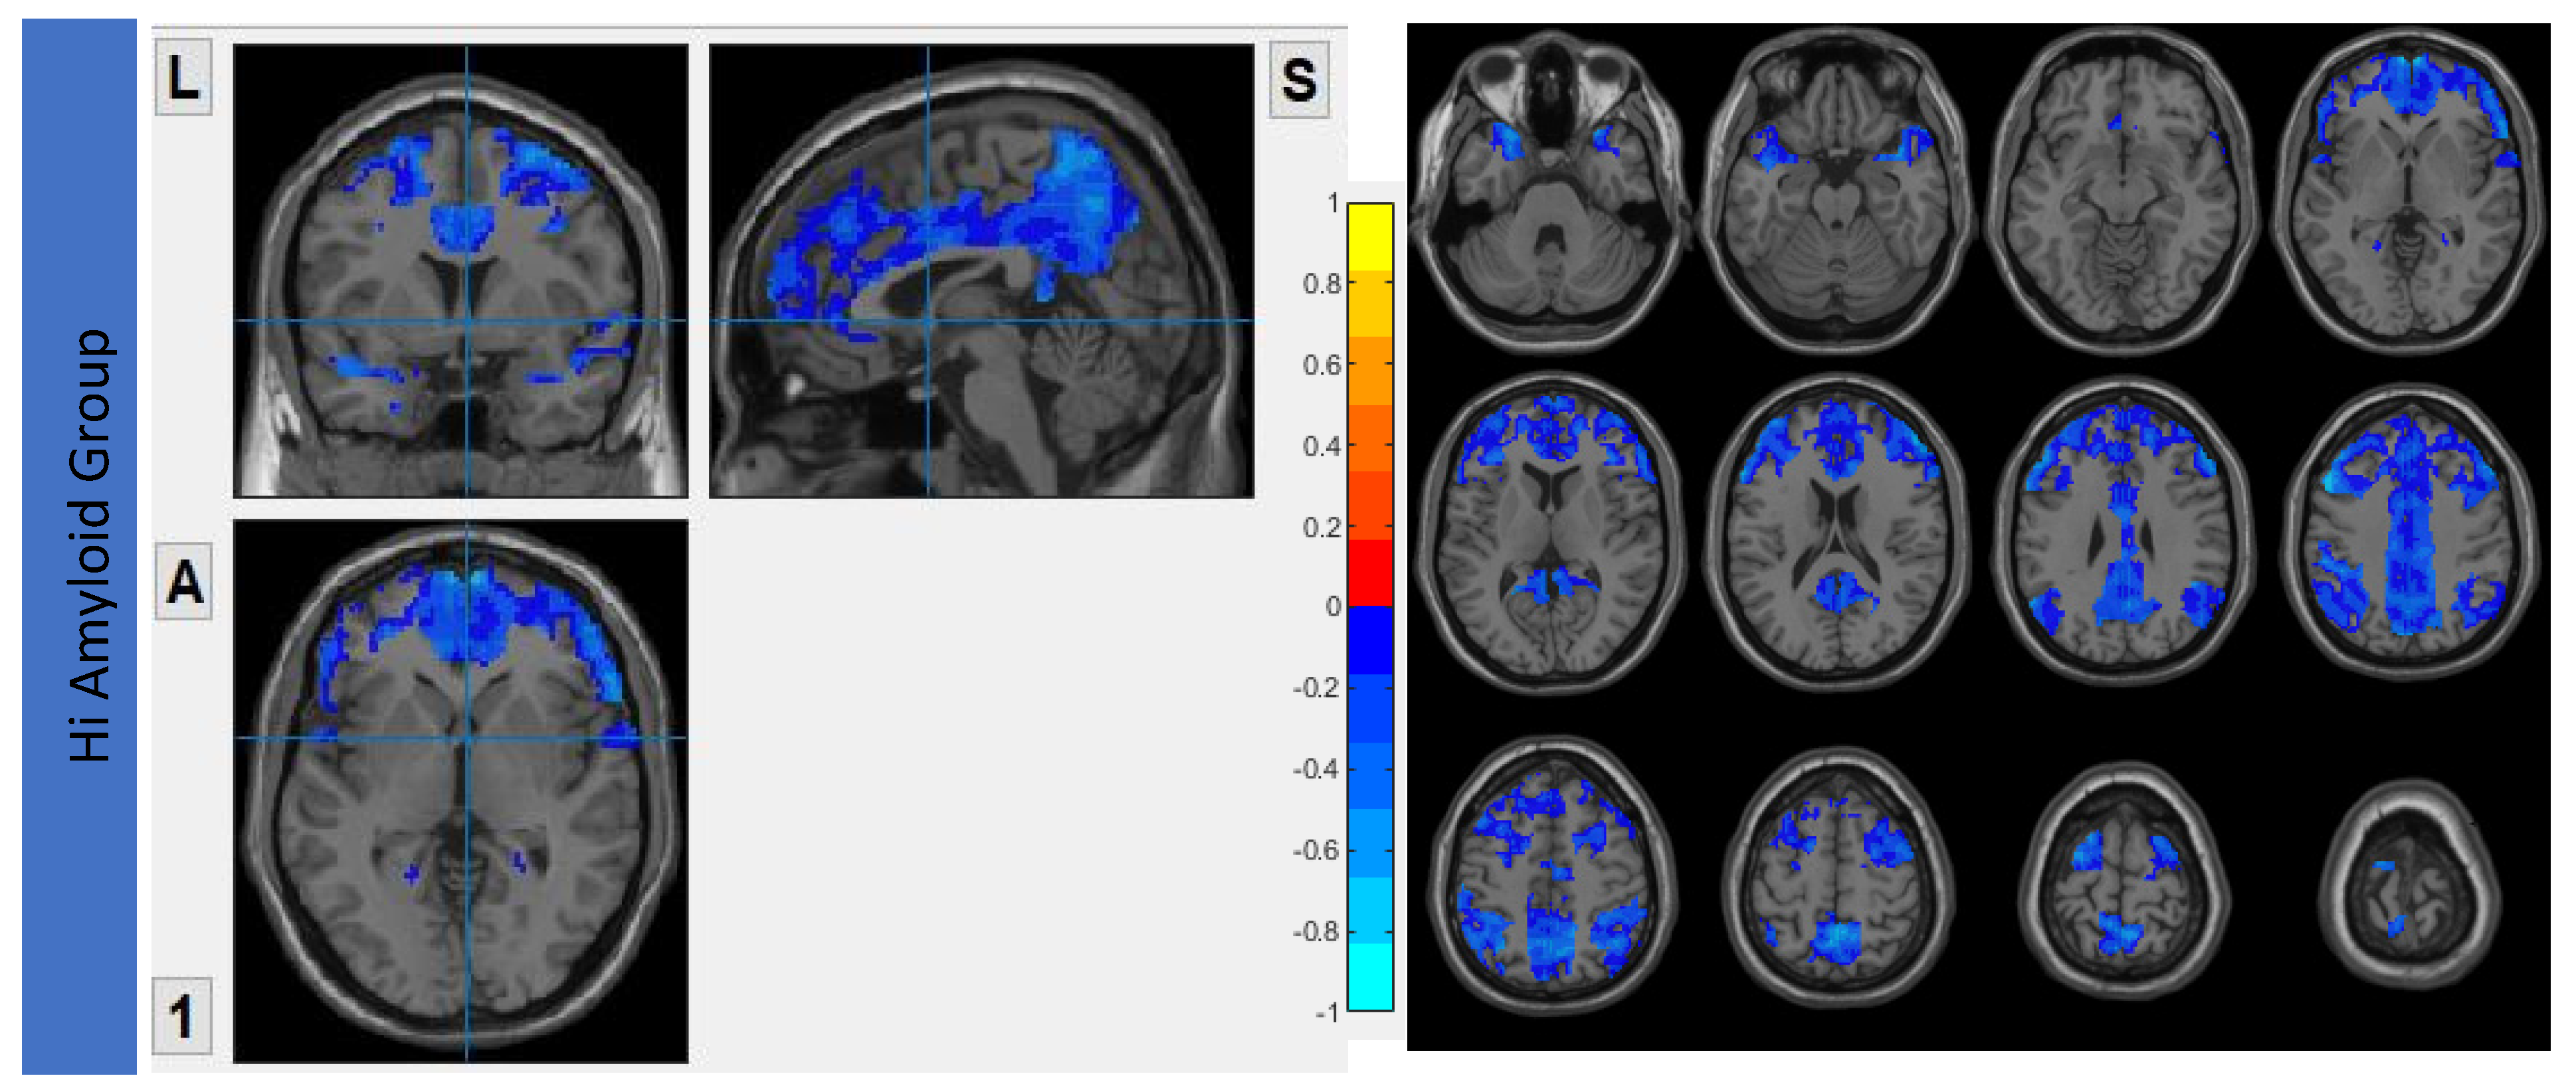

7.1. Within DMN